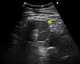

Renal infarct